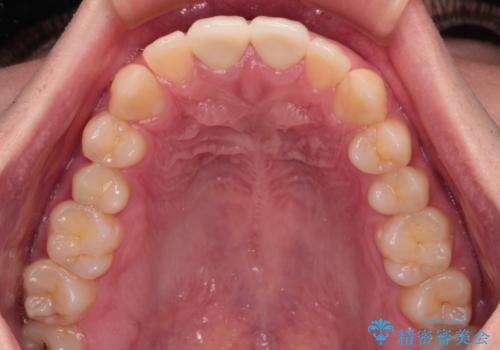

幸いにも神経組織に影響はなく、健全な状態で治療を終えることができました。

歯肉の腫脹が目立っていたため、衛生指導も並行して行い、引き締まった歯肉になりました。

外傷歯は、将来的に歯根吸収を起こす可能性があるため、定期的なレントゲン撮影により経過観察が必要となります。